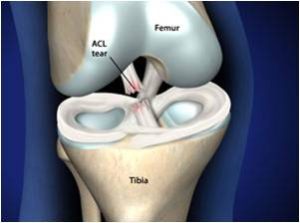

The anterior cruciate ligament (ACL) is a 3-4cm long band of fibrous tissue that connects the femur (thigh bone) to the tibia (shin bone). It helps stabilise the knee joint when performing twisting actions. The cruciate ligament is usually not required for normal daily living activities, however, it is essential in controlling the rotation forces developed during side stepping, pivoting and landing from a jump.

WHY DOES THE ANTERIOR CRUCIATE LIGAMENT FAIL TO HEAL?

Unlike other ligaments about the joint, the ACL passes through the joint and is surrounded by joint fluid. Other ligaments heal by scar formation, however due to the unique location of the ACL the bleeding is uncontained, filling the joint, causing pain and swelling. The blood irritates the knee joint’s lining to produce synovial fluid. This fluid is designed to dissolve and prevent blood clotting within the joint. Without blood clot, scar tissue does not form. The result is that the ACL rarely heals in continuity.

In the surgery a graft will be harvested to use to reconstruct the torn ligament. Usually two of the hamstring tendons are taken, but sometimes other suitable graft choices are used. This will be discussed with you prior to the operation. The remnants of the torn ACL are removed with keyhole surgery and tunnels are made in the tibia (shin bone) and femur (thigh bone) to allow the graft to be positioned across the knee. The new reconstructed ligament is then fixed at both ends to secure it in place.